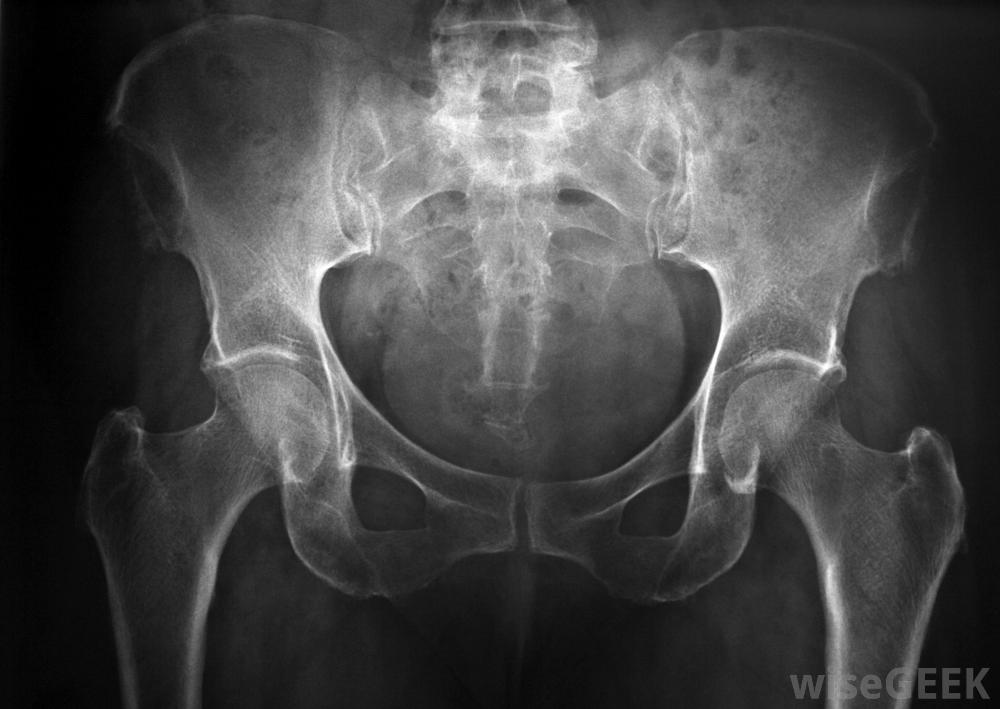

用x光檢查輸尿管支架的放置情況。

病人在支架置入期間接受全身麻醉泌尿科醫生通過將一個稱為膀胱鏡的小伸縮管插入尿道并插入膀胱來安裝輸尿管支架。然后將支架穿過膀胱鏡,放入輸尿管和腎臟。通過X光檢查確定支架是否正確放置。如果沒有,當腎結石被困在輸尿管中時,可以使用輸尿管支架。